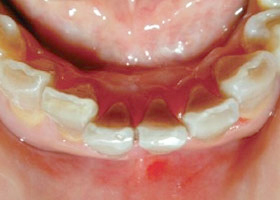

4. 使用活動式矯正裝置矯正中(矯正方式因人而異)。

5. 矯正後,上顎外暴及下顎參差不齊的情況大幅改善。